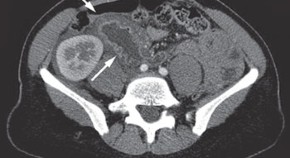

• A 33-year-old woman with a history of paroxysmal nocturnal hemoglobinuria (PNH) presented with abdominal pain, nausea and vomiting, accompanied by duodenal wall thickening seen on an abdominal CT scan and an ischemic-looking duodenal mucosa as visualized by endoscopy. She was diagnosed as having small bowel ischemia complicating PNH. Treatment with warfarin was started, but ischemic episodes recurred. Treatment with eculizumab was, therefore, proposed. This case highlights this rare gastrointestinal complication of PNH.